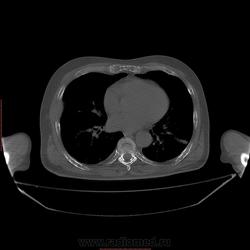

Пациент 1946 г.р., состоит на Д учете в онкодиспансере по поводу с-ч кожи (базалиома), прошел курс лучевой терапии, в 2009г на Ргенографии выявили образование 7 ребра, направили на Кт, на КТ (2009г) был выставлен д-з ГКО, пункционная биопсия не произведена. А сейчас вот такая картина, с множественными литическими очагами в костях грудного склета + образование 7 ребра, с отрицательной динамикой.

повторно взяли пациента, сняли кости таза, такая же картина- множественные очаги литической деструкции. Заключение: больше данных за миеломную болезнь.